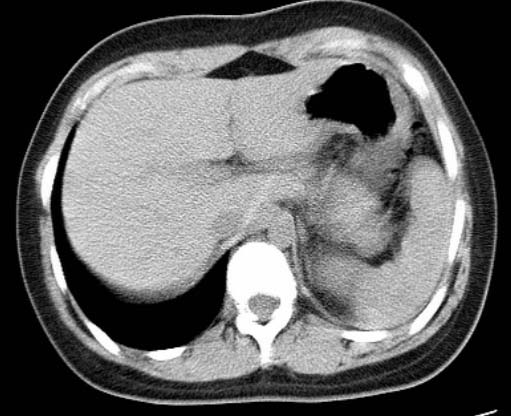

标题: CT25648:求教:是肺发育不全还是结核?

女  20岁。一月前咳血,诊“肺结核”抗痨治疗一月后,咳血停止,现复查。病人精神好。前后ct片对比未见明显变化。既往体检“正常”

1)考虑左肺结核并肺不张、支气管扩张。2)纵隔疝。

考虑左肺结核,左肺毁损,纵膈左偏,既往体检正常不可靠,tb一个月也不会这个样子的,有钙化,应该病程较长,冰冻三尺非一日之寒!

左肺发育不全。